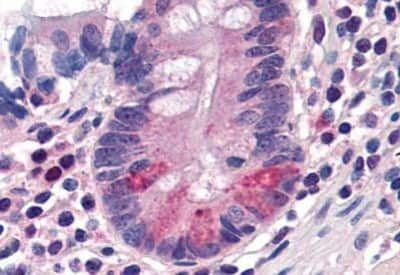

Immunohistochemistry-Paraffin: PEPT1/SLC15A1 Antibody [NBP1-39784] - Analysis of anti-SLC15A1 antibody with human small intestine, Paneth cells at concentration 20 ug/ml.